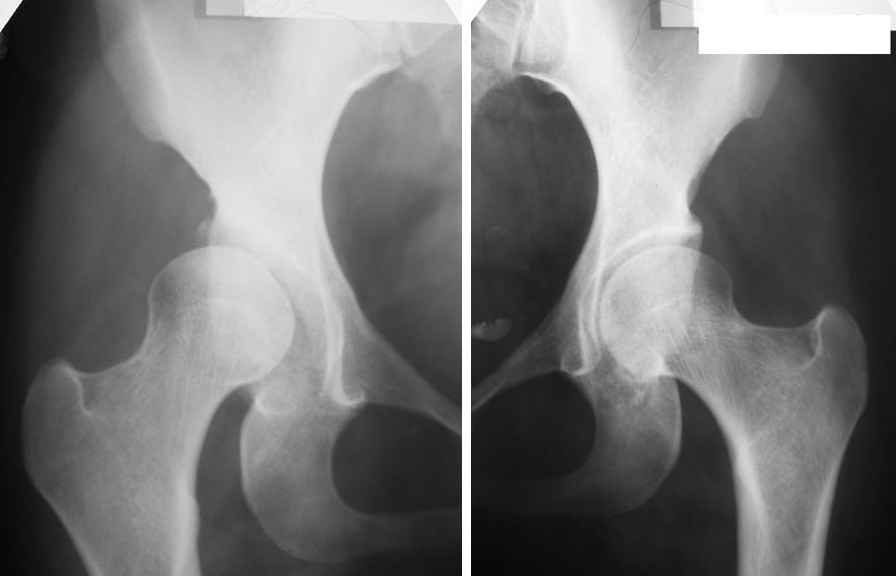

Женщина, 26 лет. Врожденный вывих обоих бедер, сколиоз

грудопоясничного отдела позвоночника 1-2 ст. Лечилась консервативно.

Работает бухгалетром. С февраля сего года отмечает периодические

умеренные боли в правой паховой области. Движения в суставах не

ограничены. Больной рекомендовано консервативное лечение. Возможные

варианты хирургических вмешательств (сроки)? Заранее благодарю!!!